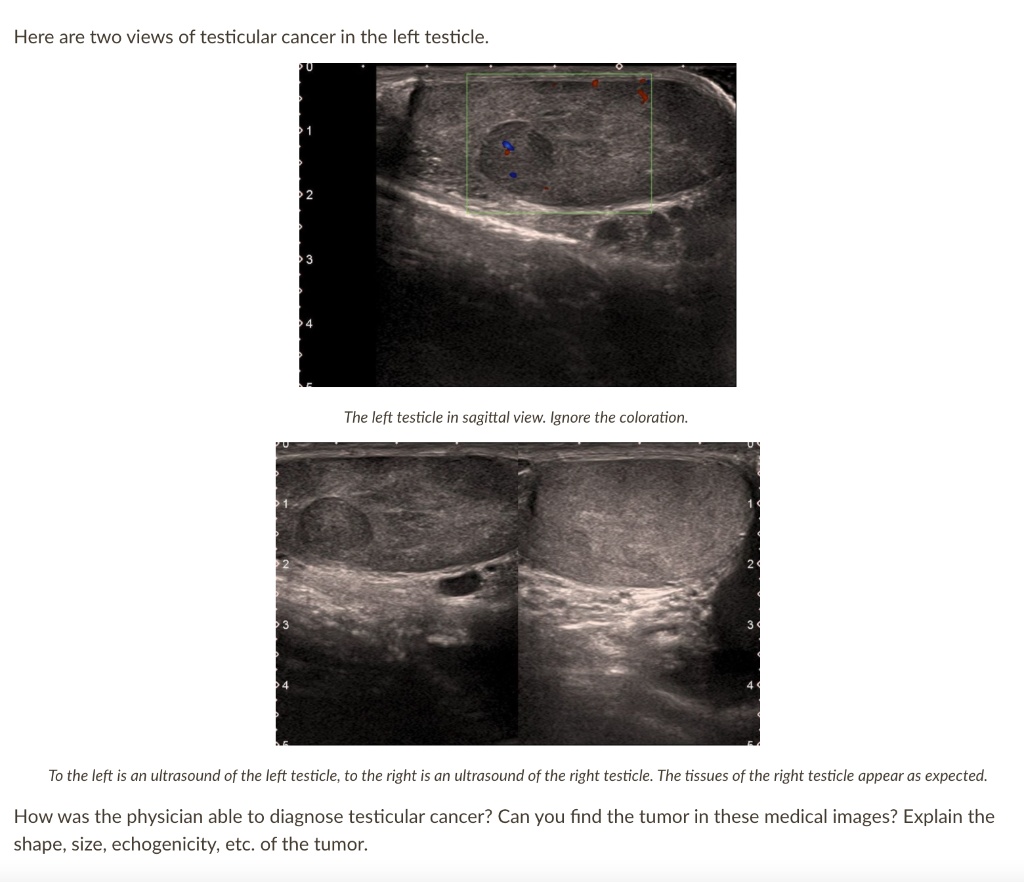

SOLVED Here are two views of testicular cancer in the left testicle How Long Does It Take To Diagnose Testicular Cancer Web while a cancer diagnosis is always serious, the good news about testicular cancer is that it is treated successfully in 95% of cases. Web testicular cancer is a growth of cells that starts in the testicles. For many other kinds of cancer, a biopsy is done before surgery. Web surgery to diagnose testicular cancer. A primary care doctor will. How Long Does It Take To Diagnose Testicular Cancer.